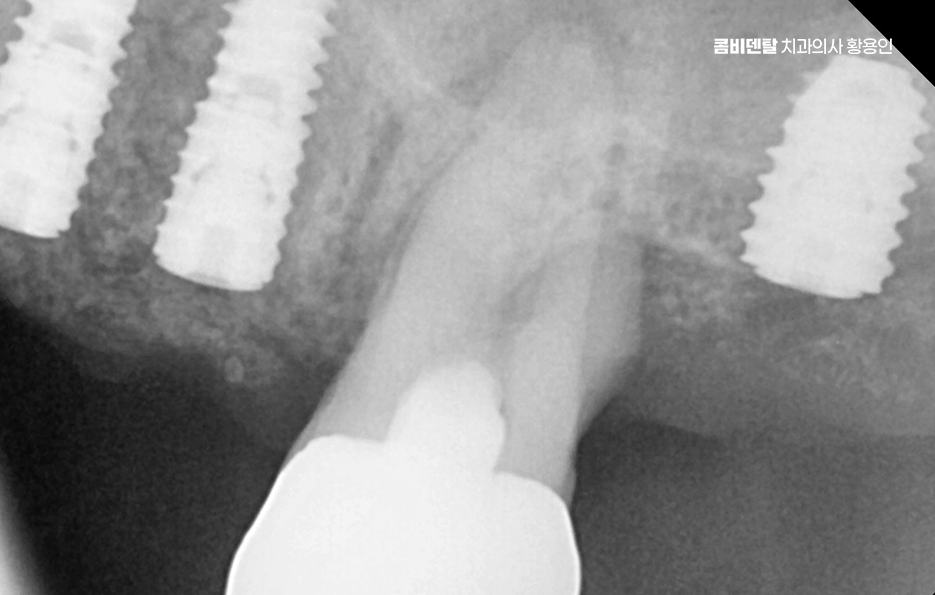

치아 발치 후 임플란트 치료 과정을 살펴보면 임플란트는 티타늄이라는 재료로 만든 인공 치근을 잇몸 뼈에 식립하고, 그 위에 보철물을 올리는 구조로 티타늄은 인체에 잘 맞는 재료라 뼈와 자연스럽게 붙는 성질이 있는데 이 과정을 ‘골융합’이라고 하고 이 골융합이 안정적으로 일어나야만 임플란트가 오래 버틸 수 있고, 자연치아처럼 역할을 할 수 있는 거예요.

치아 발치 후 임플란트 치료 과정은 처음에 CT나 파노라마 엑스레이를 통해 뼈의 양과 밀도, 신경 위치를 정확히 확인하는 것부터 시작되며 치아가 빠진 자리에 뼈가 많이 흡수되어 있다면, 임플란트를 심기 전에 뼈이식을 먼저 해야 할 수 있지만 반대로 뼈 상태가 좋다면 임플란트를 심고, 보통 3개월 동안 뼈와 잘 붙을 때까지 골융합 과정을 기다리게 되며 골융합이 잘 이루어진 뒤에는 그 위에 지대주라는 연결 부품을 끼우고, 그 위에 최종 보철물을 씌우면서 치료가 마무리되고 있어요